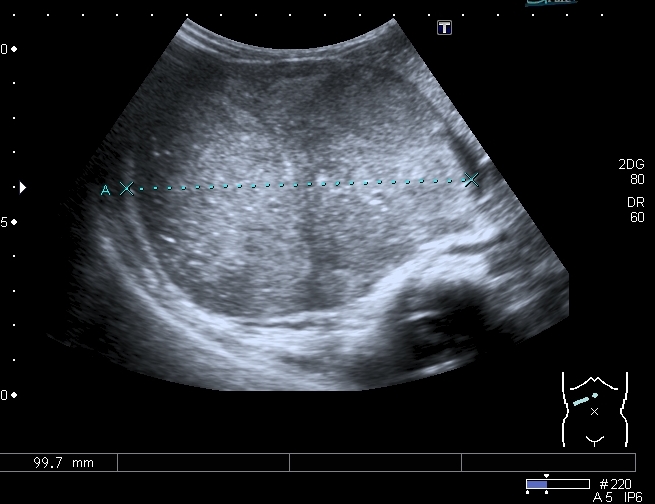

Правая почка нашлась в полости таза, верхним полюсом прилежала к образованию, но не была с ним связана.